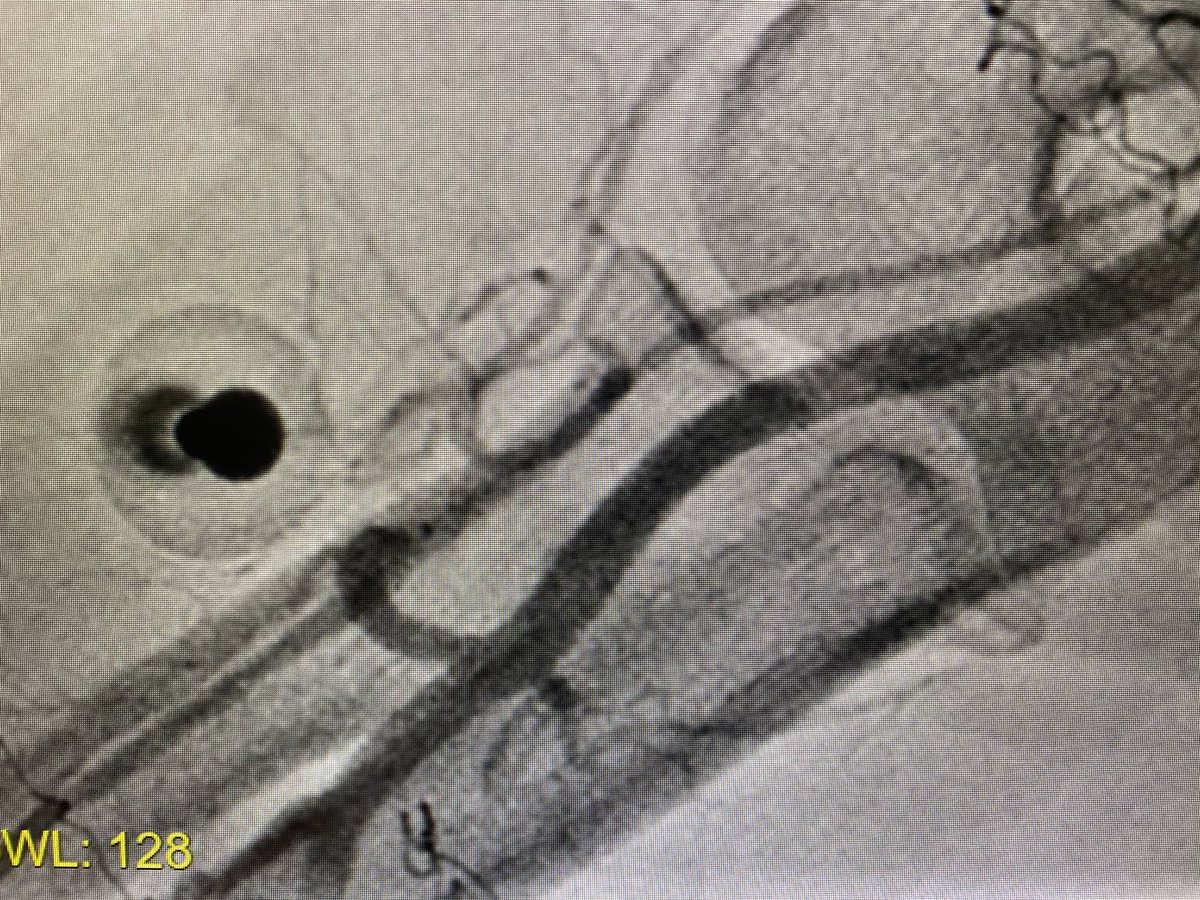

#ICFIT Subtotal occlusion of anomalous RCA (take off anterior/downward from left sinus, just beside LM stem). Diagnostic made in OSH (also crossover from radial to femoral) but report said they couldn’t PCI 🤷🏻‍♂️. Went femoral w/ multiples guides. Could probe and understand anatomy

evandrofilhobr's tweet image. #ICFIT Subtotal occlusion of anomalous RCA (take off anterior/downward from left sinus, just beside LM stem). Diagnostic made in OSH (also crossover from radial to femoral) but report said they couldn’t PCI 🤷🏻‍♂️. Went femoral w/ multiples guides. Could probe and understand anatomy